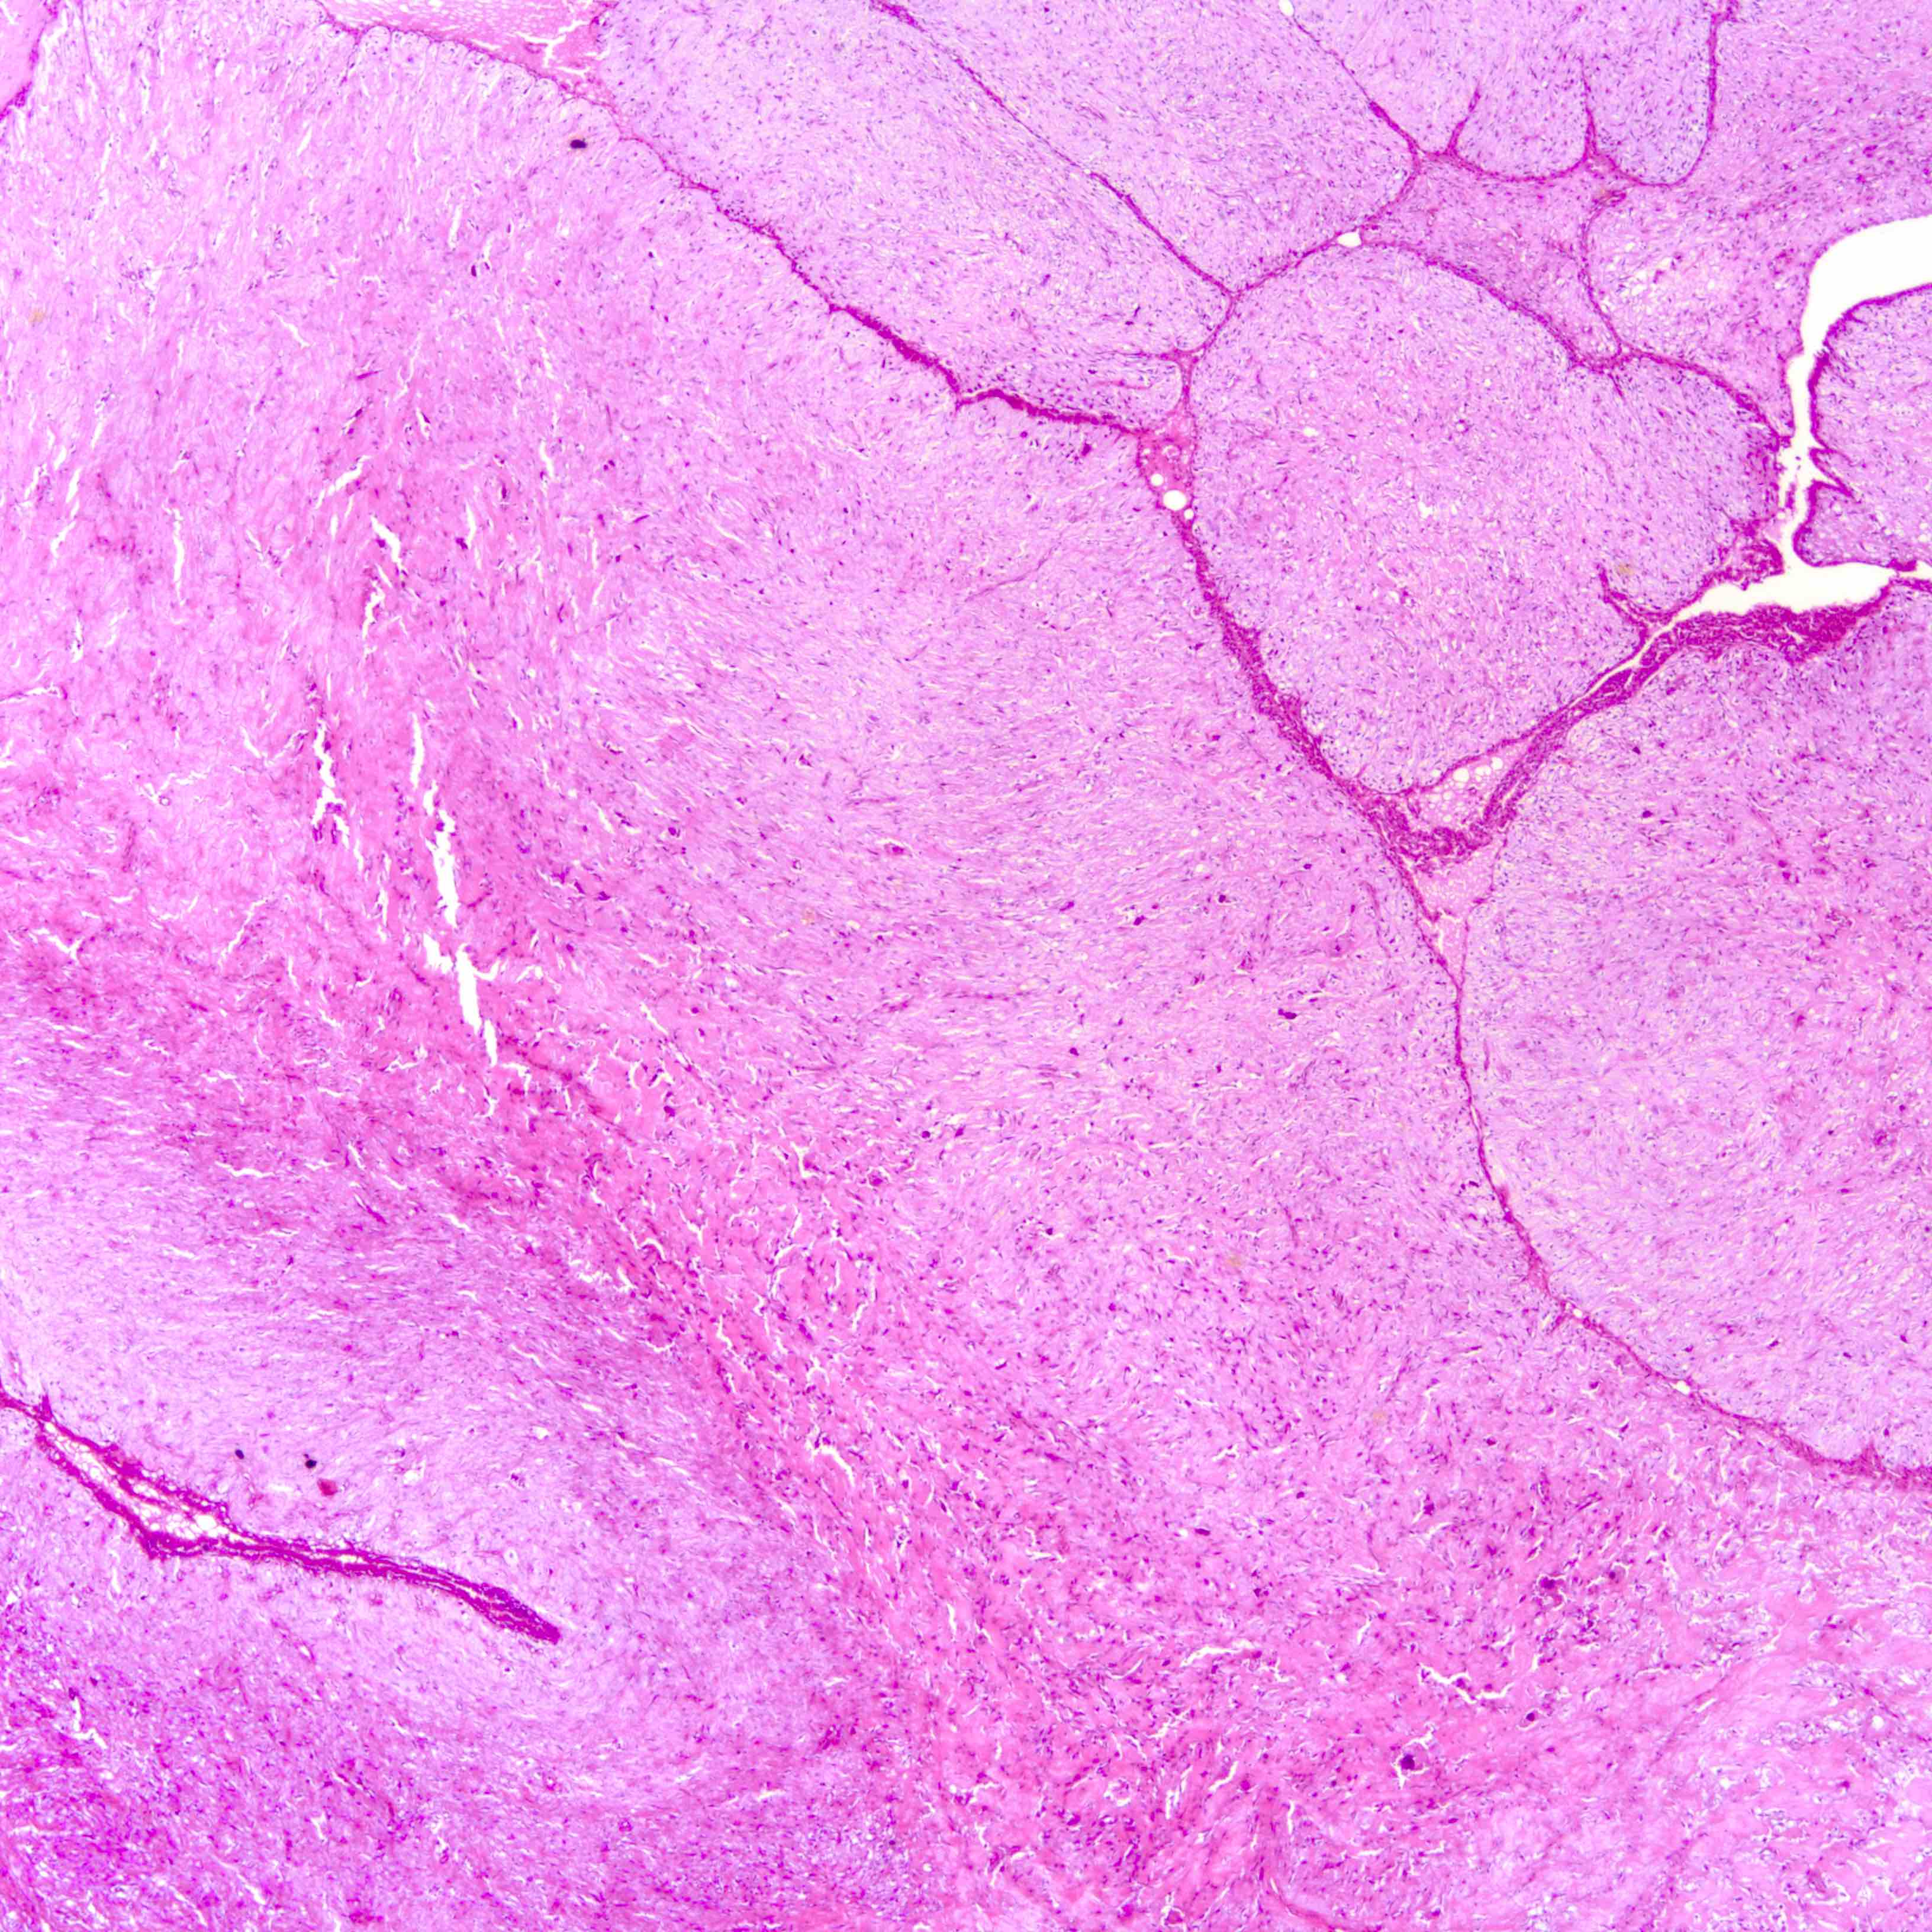

Microscopic (histologic) images

Contributed by Joshua J.X. Li, M.B.Ch.B. and Gary M. Tse, M.B.B.S.

Borderline phyllodes tumor